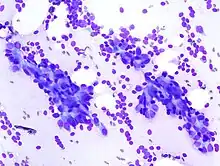

| Histopathologic image of breast fibroadenoma. Core needle biopsy. H&E stain. | |

The diagnostic findings on needle biopsy consist of abundant stromal cells, which appear as bare bipolar nuclei, throughout the aspirate; sheets of fairly uniform-size epithelial cells that are typically arranged in either an antler-like pattern or a honeycomb pattern. These epithelial sheets tend to show typical metachromatic blue on Diff-Quik staining. Foam cells and apocrine cells may also be seen, although these are less diagnostic features.[9][11] The gallery images below demonstrate these features.

Histopathologic image of breast fibroadenoma. Core needle biopsy. Hematoxylin & eosin stain. -